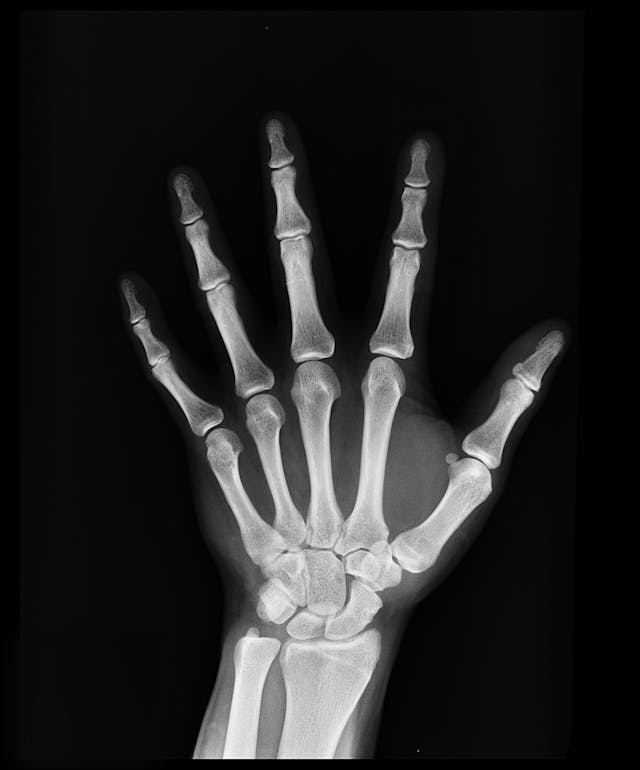

- 성장판 검사 방법 엑스레이를 통한 골연령 검사로 성장판의 상태와 남은 성장 가능성을 평가할 수 있습니다. 왼손 손목 X-ray가 가장 일반적으로 사용됩니다.